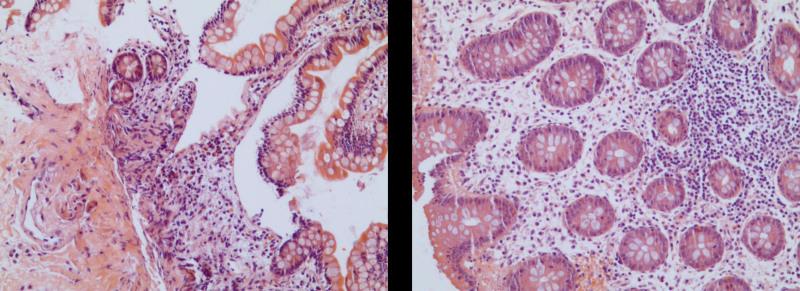

We herein report a case of a 29-year-old woman who presented with abdominal pain, nausea, and vomiting, with no history of adverse reactions to any allergens. Laboratory test results revealed a normal count of peripheral blood eosinophils. Ultrasound and computed tomography revealed thickened intestinal walls and ascites in both the abdominal cavity and the pelvic cavity. Multiple endoscopic biopsies targeting several swelling segments of the intestinal wall revealed no increase in the number of eosinophils.

EoGE should be considered scrupulously, even if the count of eosinophils is in the normal range and the endoscopic biopsy is negative. Obtaining pathology of ascites as much as possible and taking a multisite biopsy sample, including both targeted and random biopsies, may improve the diagnostic rate.

我们在此报告一例29岁女性患者,她出现腹痛、恶心和呕吐症状,既往无任何过敏原不良反应史。实验室检查结果显示外周血嗜酸性粒细胞计数正常。超声和计算机断层扫描显示肠壁增厚,腹腔和盆腔均有腹水。针对肠壁多个肿胀节段进行的多次内镜活检显示嗜酸性粒细胞数量未增加。

即使嗜酸性粒细胞计数在正常范围内且内镜活检为阴性,也应谨慎考虑EoGE。尽可能获取腹水病理,并进行多部位活检取样,包括靶向活检和随机活检,可能会提高诊断率。